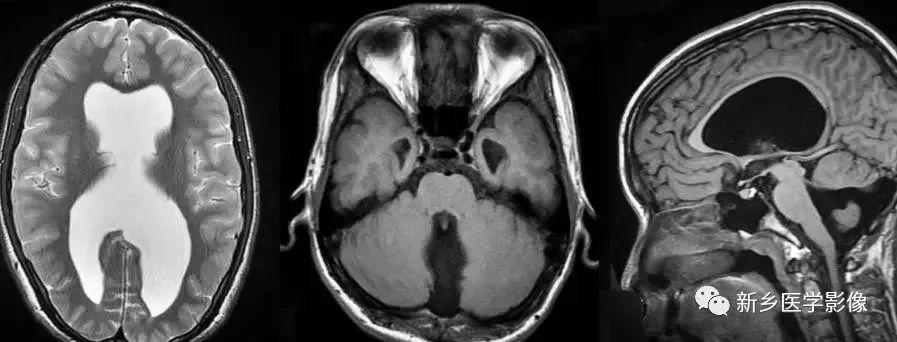

(3)无脑回和巨脑回

无脑回和巨脑回是一组因神经元移行异常所致的脑回发育异常。巨脑回也称平滑脑。巨脑回指有部分脑回存在,这些脑回异常增大增宽.脑沟变浅。巨脑回主要位于额、颞部。无脑回上要位于顶、枕部。

临床上,无脑回和巨脑回畸形患儿均表现有小头畸形和轻微的面部异常,完全无脑回畸形常在两岁前死亡.不完全无脑回畸形存活常能长期。

CT和MR均能够很好显示无脑回和巨脑回畸,表现为大脑半球表面几乎呈光滑状,仅可见少数宽阔、粗大、平坦的脑回,脑沟缺如.脑灰质增厚,脑白质变薄,灰白质分界面异常平滑,见不到白质向灰质内伸入的现象。常见透明中隔腔存在.侧脑室扩大,蛛网膜下腔增宽。